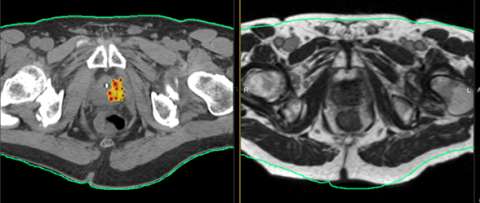

After a brief stay in the recovery room the patient has a CT simulation where the placement of the flexiguides is confirmed. Once the images of the implant are obtained the patient waits for the customized treatment plan to be generated.

HDR Dose Distribution

This is a transverse view of a typical prostate implant showing the radiation "isodose" levels. The blue dots are the superimposed dwell positions along the 17 catheters. (imagine looking end on at a string of beads).

Notice the central area of reduced dose created by the ability to adjust the time the source spends in the 5 interior catheters to spare the urethra (outlined with yellow dots). Also notice the space between the implant and the rectal points. In its natural position, the prostate lies on top of the anterior rectum, separated by a thin layer of tissue, called fascia. The non-fixed template technique allows the physician to slightly lift the prostate away from the rectum, reducing rectal dose. The HDR system allows for dose adjustments and the treatment is delivered in minutes while the rectum is empty. These advantages over permanent seeding are the reasons why the leading centers that perform HDR implants are all reporting very low, if any, rectal complications. Permanent seeds can shift from their original ideal positions resulting in the actual dose distribution not being like the approved pre-plan. With the HDR system, the prostate is held in position by the catheters and the catheters are held in position by the template. If the patient moves, the implant moves with him. HDR is the most accurate method of radiation dose delivery available.